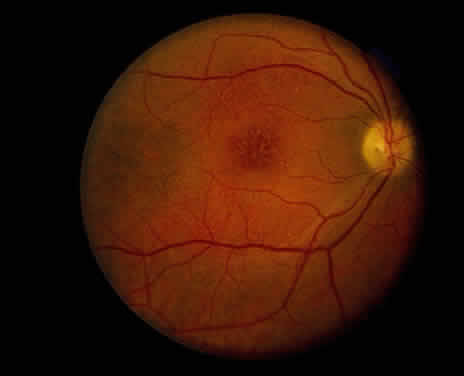

Clinically, retinal schisis presents with decreased central visual acuity, absolute scotomas, or both.1,33,38 Children may have strabismus and nystagmus.25,47 As in FEVR, but in contrast to Wagner and Stickler syndrome, the refraction tends to be hypermetropic (“hypermetropic amblyopia”).1,25,26,31–34,40,48 On biomicroscopic examination, edema and cystic central macular schisis of the retina are apparent in virtually all cases.37,38 Loss of macular reflex, which may be an early sign,34,35 is followed by wheel-like formation,37 a multicystic radiate appearance (Fig. 1),38 pigmentary degeneration, and cystic macular atrophy (Fig. 2).38 These macular changes, not bullous schisis per se, determine visual loss in patients often in the fourth or fifth decade of life.51